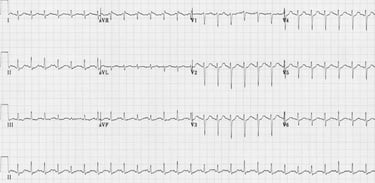

Above is a traditional ECG strip, with the line running through the middle on each view established as the “baseline for electrical activity” or the isoelectric line.

Each lead, or view looks at unique parts of the heart’s electrical activity, which is why some rhythms differ from others.

The rhythms seen above are created by electrical vectors in which the heart’s electrical activity is detected through vectors which point to the lead placements.